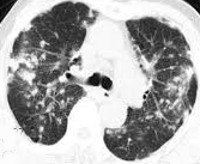

• Рентгенография или КТ легких. На рентгенограмме или компьютерной томограмме видны небольшие темные круглые области, в основном в периферических частях легких. Корневые и средостенные лимфатические узлы часто увеличены. Возможно плевральный отек.